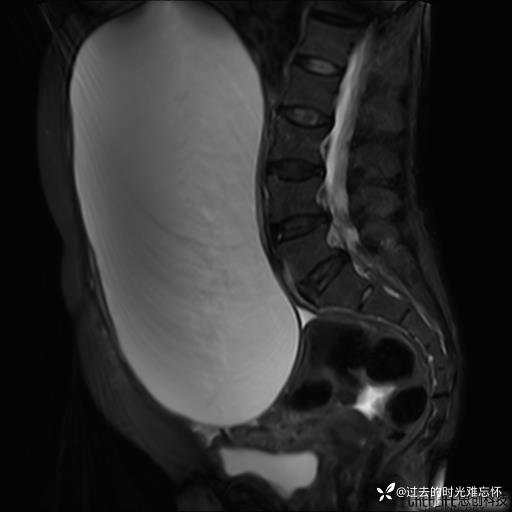

患者性别:女

患者年龄:65岁

主诉: 发现腹部隆起半年余。无其他明显不适。

浆液性囊腺瘤 (22)